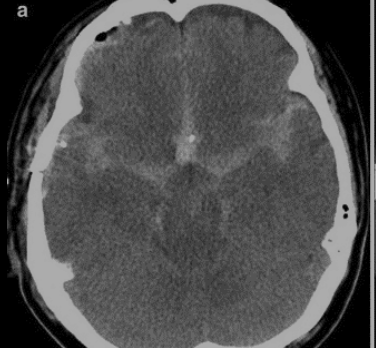

HSA

Falso realce